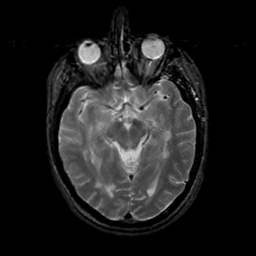

MR Study #18, July 21, 1991 -- Slice #21